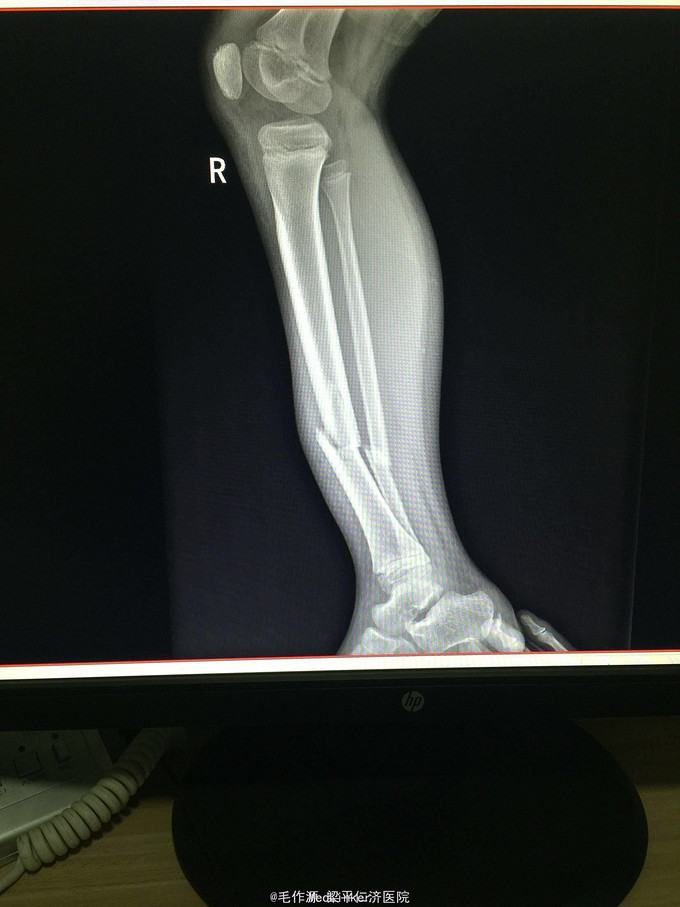

右下肢肿胀、畸形,局部压痛明显,可扪及骨擦感及骨擦音,轴向扣痛(+),有假关节活动,右足背动脉可扪及,肢体远端血供及感觉正常。 右下肢DR正侧位示:右胫腓骨中下段骨折。

1、右胫腓骨中下段骨折(R)